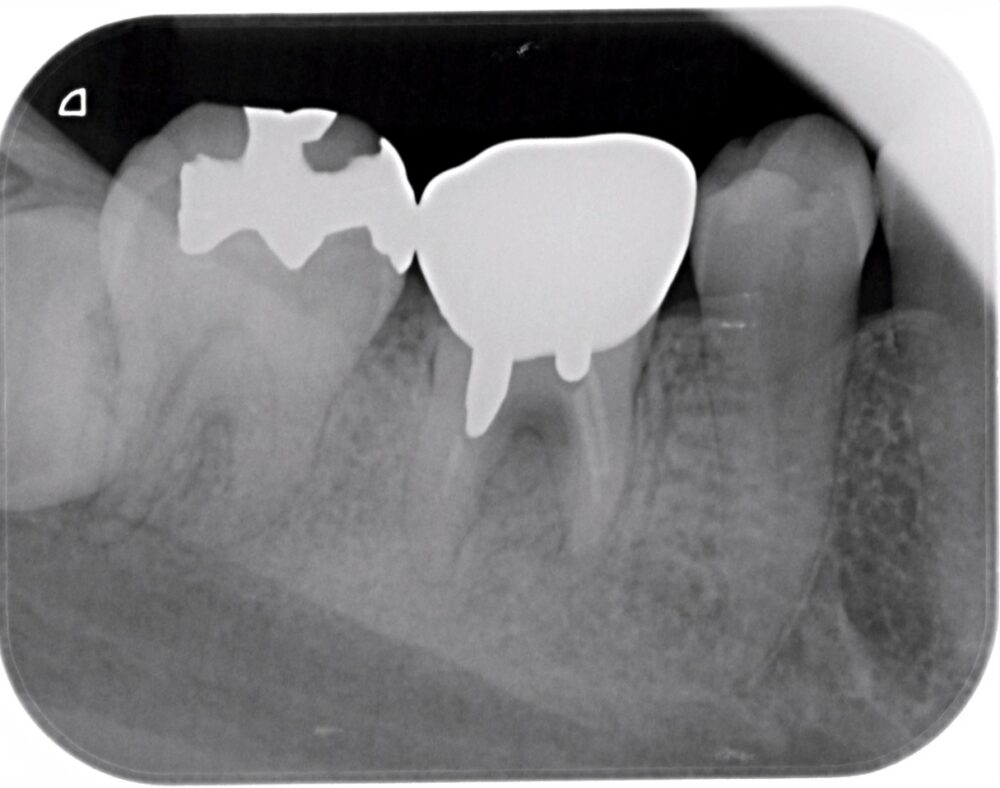

症例1:パーフォレーションリペア症例

(歯の中に大きな穴が空いてしまっているのを埋めて再生を促す治療)

歯に穴が空いていて骨に炎症がある状態 |

CTでも歯の周囲に骨がないのが分かる。 |

BEFORE |

| 医院の診断 | 虫歯の再発、慢性根尖性歯周炎、遠心根人為的穿孔 |

人為的根穿孔を起こした部分に感染を起こしており、歯周ポケットが9㎜ありました。 ラバーダム防湿とマイクロスコープを使用して丁寧に治療を行いました。 殺菌性があり歯を補強することのできるMTAという根管充填材料を使用して、歯周ポケットは2㎜に改善しました。 |